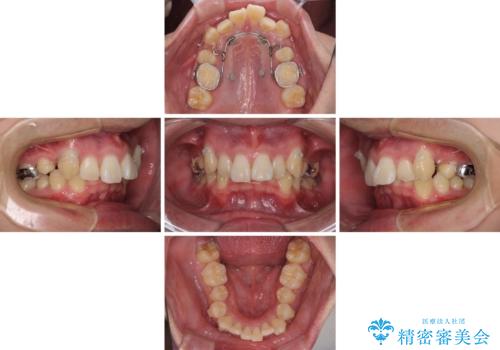

八重歯の抜歯矯正 インビザラインを用いて気になる歯並びを改善

- 八重歯を気にして来院された患者様です。

顕著な上顎の八重歯とディープバイトであったため、上顎の左右第一小臼歯を抜歯することとしました。

犬歯歯根の位置や奥歯の咬み合わせから、ワイヤー装置での治療を強くおすすめいたしましたが、ご本人の強い希望により、妥協的な仕上がりとなることを了解いただき、インビザラインにて矯正治療を行うこととしました。

インビザライン単体で、左右ともに移動の難しい位置に歯根のある犬歯を整えるのは困難と判断し、補助装置を併用することとしました。

ディープバイトや奥歯の咬み合わせなど、インビザライン矯正では限界がありワイヤー装置での治療に及ばない仕上がりとなりました。

ただし、患者様としては八重歯や、それに伴う唇の閉じにくさが改善されたとのことで、納得いく状態での治療終了となりました。